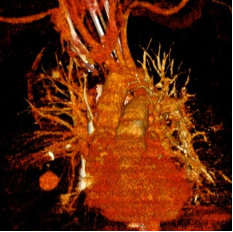

Cas 2 : Pseudo-anévrysme sur branche sous-segmentaire de l’artère pulmonaire droite

après multiples drainages pour infection pleuro-pulmonaire sévère. Contrôle avant et après

embolisation par coil.